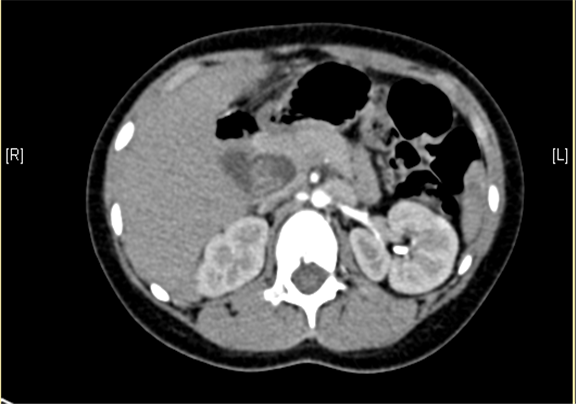

术前CT检查:

动脉期

静脉期

上腹部增强CT:1. 肝内部分胆管-肝门部胆管-胆总管扩张,符合先天性胆管扩张症2. 胆总管下段腔内结节状略高密度影,伪影?结石?3. 胆囊壁略厚,提示胆囊炎可能。